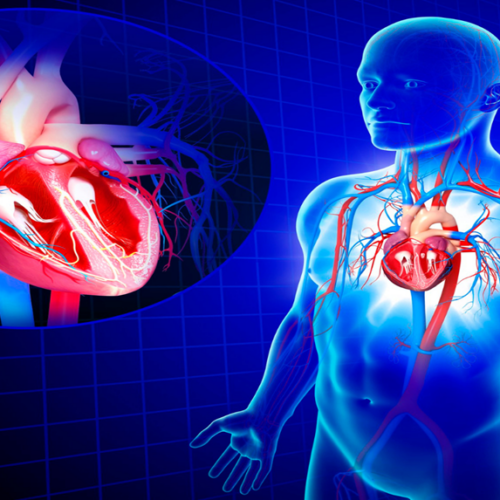

Sistema de conducción eléctrico del corazón

El sistema de conducción eléctrico del corazón es “un grupo de células especializadas, las cuales generan pequeñas corrientes eléctricas que van estimulando a través de su red a los músculos del corazón"